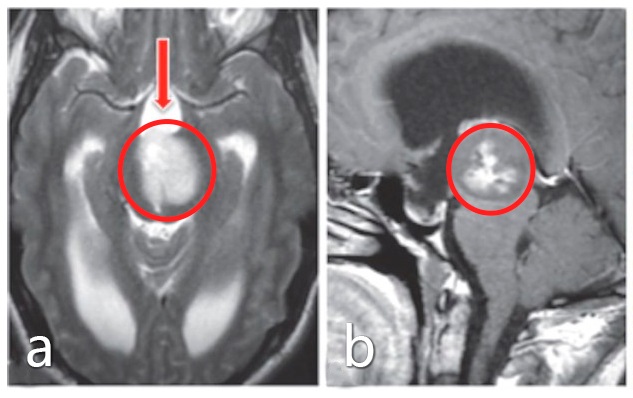

术前:a、b图患者术前MRI影像显示脑干中脑较大占位,肿瘤占位引起梗阻性脑积水

手术入路和体位:额叶正中颅骨切开术,仰卧位。a图箭头指示了额叶半球入路,f图术中照片显示,肿瘤主要通过椎板末端进入,高于保留的前交通动脉。

术后:d、e图MRI影像提示肿瘤得到全切,病理结果为1级毛细胞型星形细胞瘤。无围手术期并发症,无神经和认知缺陷,术后5年随访未见复发。